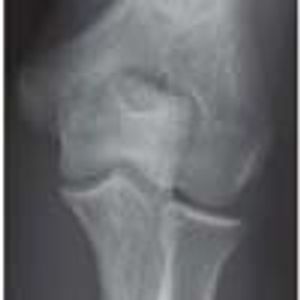

A 10-year-old boy injured his left elbow during football practice. He subsequently had pain with normal range of motion of the elbow.